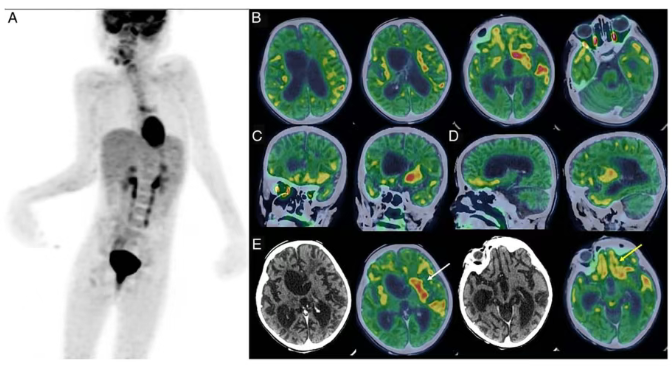

研究团队获得的脑代谢显像数据,揭示了此类疾病状态下大脑特有的代谢模式,包括广泛性代谢减低与局灶性代谢增高的特征性表现。这一成果不仅验证了FDG PET/CT在罕见及复杂神经系统疾病研究中的应用价值,也进一步拓展了核医学技术在神经科学前沿探索中的能力边界。